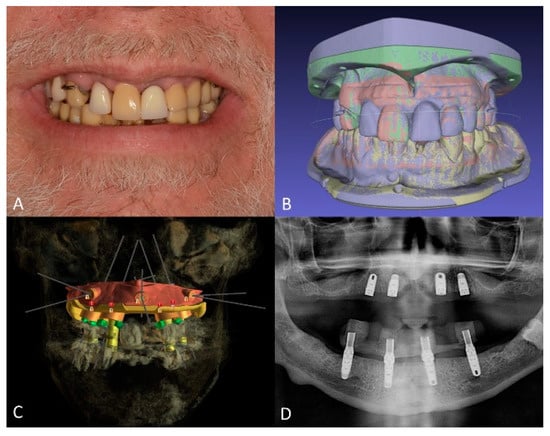

Full-Mouth Rehabilitation of a Patient with Sjogren’s Syndrome with Maxillary Titanium-Zirconia and Mandibular Monolithic Zirconia Implant Prostheses Fabricated with CAD/CAM Technology: A Clinical Report

2. Materials and Methods

3. Results